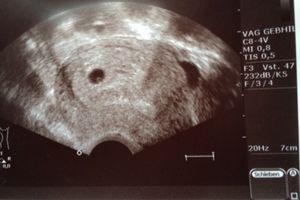

Der Embryo wird normalerweise am Ende der 6. Schwangerschaftswoche (SSW) sichtbar, wenn er sich am Rand der Fruchthöhle entwickelt. In dieser Phase kann man möglicherweise bereits die Anlage des winzigen Embryos erkennen.

– Am Ende der 6. SSW lässt sich möglicherweise schon die Anlage des winzigen Embryos am Rand der Fruchthöhle erkennen.

Am Ende der 6. SSW lässt sich möglicherweise schon die Anlage des winzigen Embryos am Rand der Fruchthöhle erkennen. Es kann jedoch sein, dass noch nichts sichtbar ist, insbesondere wenn das Baby eher am Rand sitzt.